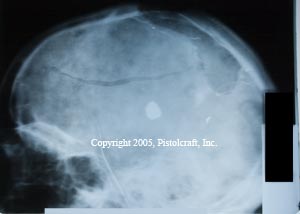

.380 Wound X-Rays

These x-rays are of a patient who received a contact wound from a .380 caliber firearm.

Note that this patient is still alive, and functions with a deficiency of about 30%.

The deformation of the brain is significant, and the bullet clearly visible in the picture.